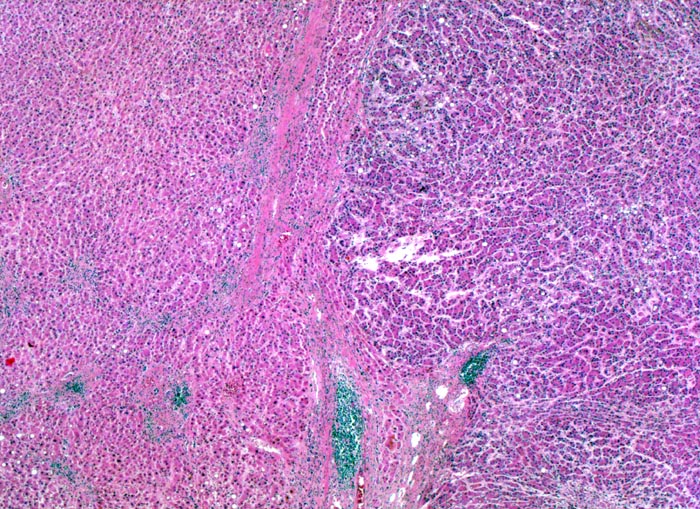

Morphologie: Makroskopisch imponiert das hepatozelluläre Karzinom als solitäre grosse Tumormasse, als zahlreiche zirrhoseartige Knoten oder als scharf begrenzter Knoten mit oder ohne Kapsel. Die tumorfreie Leber ist in der Mehrheit der Fälle zirrhotisch umgebaut. Mikroskopisch bilden die Tumorzellen mehr als 2 Zellen breite Trabekel ( 1237), kompakte Tumormassen ( 1229) oder pseudoglanduläre Strukturen (dilatierte Canaliculi) ( 1212)( 1199). Desmoplastisches Bindegewebe fehlt meist. Innerhalb des Tumors fehlen Portalfelder. Es finden sich lediglich Arterien. Etwa bei der Hälfte der Karzinome lässt sich intrazytoplasmatische oder intracanaliculäre Galle ( 1238) nachweisen. Immunhistochemisch lassen sich mit einem polyklonalen Antikörper gegen Carcinoembryonales Antigen (CEA) Gallecanaliculi zwischen den Tumorzellen nachweisen. Die Tumorzellen bilden keinen Schleim.

Innerhalb des Tumors Blutgefässe, aber keine Portalfelder.

Die Tumorzellen bilden Trabekel, welche überwiegend mehr als 2 Zellen breit sind und Pseudodrüsen.

Sinusoidartige Blutgefässe mit Endothelauskleidung verlaufen zwischen den Trabekeln und den Pseudodrüsen.

Die Tumorzellen erinnern an normale Hepatozyten, sind aber kleiner als die Hepatozyten und die Kern-Zytoplasmarelation ist deutlich erhöht. Das Zytoplasma ist basophiler als das der angrenzenden Hepatozyten.

Galle ist sichtbar in den Pseudodrüsen.

Tumorfreies Parenchym mit chronischer viraler Hepatitis (B und D): dichtes chronisches Entzündungsinfiltrat in den Portalfeldern übergreifend auf das Parenchym (Interfacehepatitis). Spärliche intralobuläre Entzündung mit Einzelzellnekrosen (Apoptosen). Fibrose der Portalfelder mit Septenbildung und unvollständigem zirrhotischem Umbau. Geringe gemischttropfige Verfettung des Leberparenchyms.